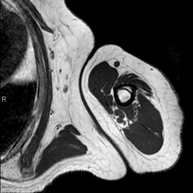

- Arm MRI

Examination to study injuries to tendons, muscles and peripheral nerves. Also useful in the study of tumours. It lasts approximately 20 minutes. It is a radiation-free procedure.